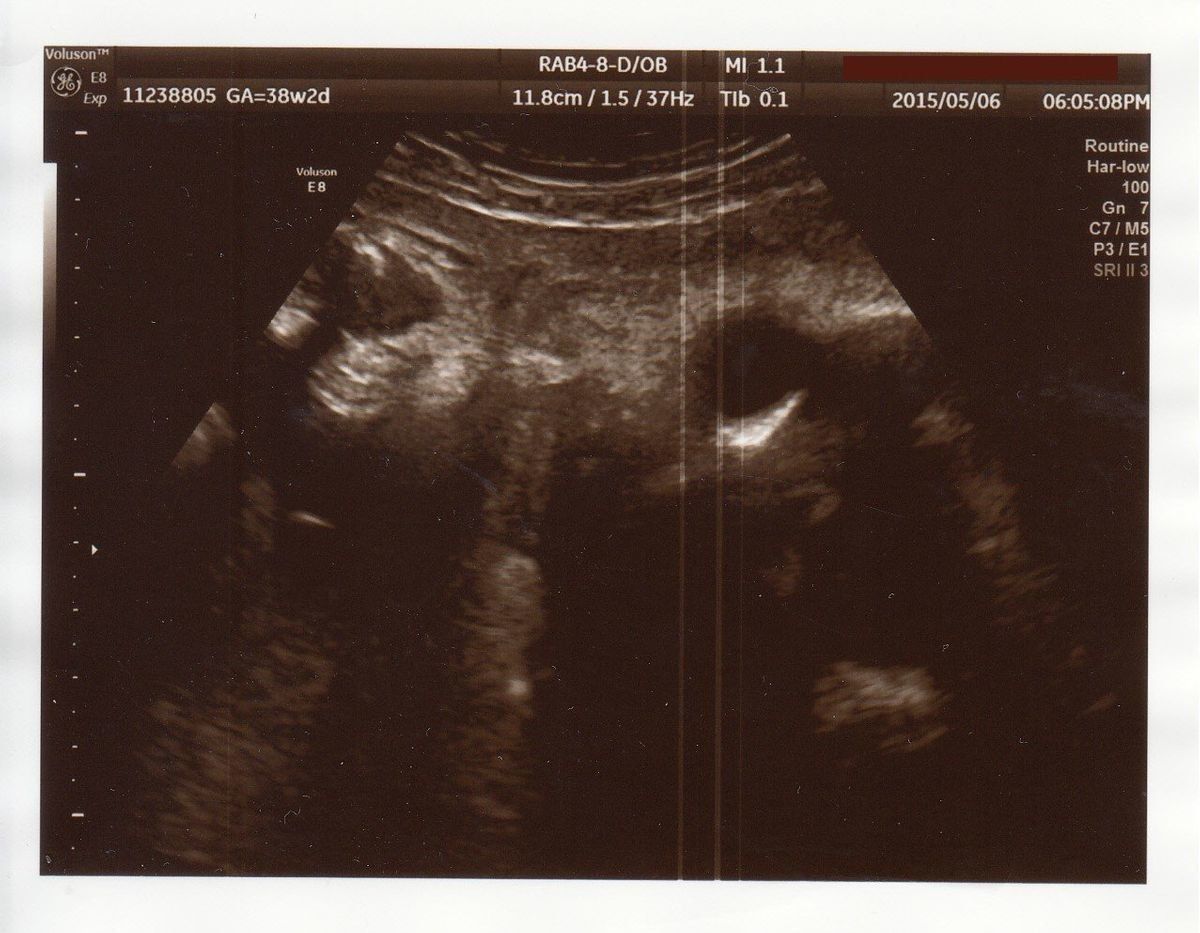

出産直前! - 妊娠38週目のエコー写真

出産前日のエコーです。真ん中の薄い線が背骨、上のところが腰だと思います。この頃は、赤ちゃんの頭は私の骨盤の方にあり、顔を見ることはできませんでした。

赤ちゃんの体重がまったく増えなくなり、37週で管理入院することになりました。赤ちゃんの推定体重は2000g程度で、誤差を含めると2000g以下の可能性もあり、低体重児になってしまいます。ちょうどよく大型連休に入り、夫が家で上の2人の子どもの面倒を見ることに。病院の食事は薄味だけどおいしくて、カロリー計算も完璧。赤ちゃんの体重を増やそうとたくさん食べていた私ですが、入院中に2kgやせてしまいました。

そして、入院7日目の朝に陣痛が開始。そのままお昼の12時に出産しました。3人目だけあって、陣痛から出産まではスムーズ。推定体重が2000g前後だと言われていた赤ちゃんでしたが、生まれてみると2600g以上あって、医師も私もびっくり。赤ちゃんは用意されていた保育器に入りましたが、特に異常もなく、翌朝には普通のベビーベッドに移されました。

遠くの大学病院まで転院しましたが、特別な医療行為の必要なく、妊娠38週3日に、体重2682g、身長46.5㎝で、頑張って生まれてきてくれた赤ちゃん。出産までヤキモキしましたが、無事に生まれてきてくれたことに本当に感謝の気持ちです。そして、上の子2人と夫は、濃密な3人だけの大型連休5日間を過ごし、きずなも深まりました。4人目は考えていないので、これが最後の出産となりそうですが、ちょっと特別な体験になりました。